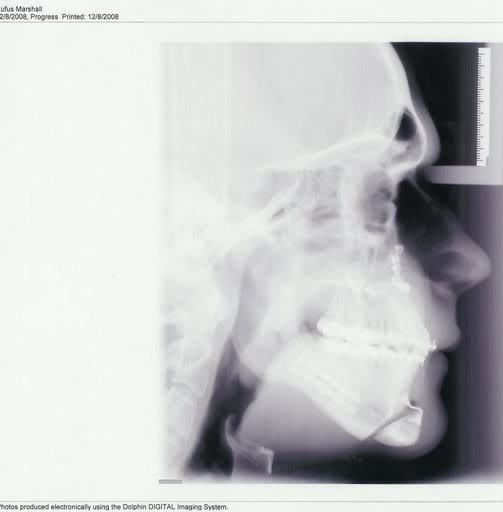

rufus

+1y

I did on December 2nd... Its custom, you know.... they C-Notched my chin and added a little length to my top and lower jaw. Check out my Post-Ops